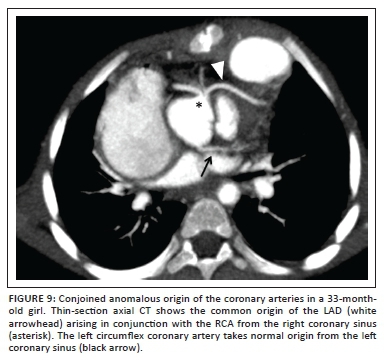

Coronary artery anomalies in TOF have an incidence of 5% - 12%13 and, whilst they in themselves do not present any risk of ischaemia or sudden death, surgical morbidity and mortality are significantly increased when they cross the RVOT. When undiagnosed, these vessels are at significant risk of surgical injury during right ventriculotomy or RVOT repair. The most frequently encountered coronary artery anomaly is left anterior descending (LAD) or accessory LAD arising from the right coronary artery (RCA) or right sinus of Valsalva14 (Figure 9) that crosses the RVOT to reach the anterior interventricular groove. The second-most common anomaly seen in most studies is that of a single coronary ostium from one of the sinuses of Valsalva (left, right or non-coronary sinus); these may or may not traverse the RVOT.

Surgical repair can be successfully contemplated even in the presence of a major coronary artery anomaly, provided that the surgeon is made aware thereof. In most instances, proximal coronary anatomy is effectively and reliably demonstrated at echocardiography15 except in instances of previous palliation, late TOF repair or reoperation resulting in a suboptimal acoustic window, or where the coronary arteries pursue an intramyocardial course.

Cardiac CTA, when ECG synchronised (see section above entitled 'Cardiac CTA protocols'), is an alternative non-invasive modality of high diagnostic performance and accuracy, to demonstrate coronary artery origins, their course and spatial relationships to adjoining structures.